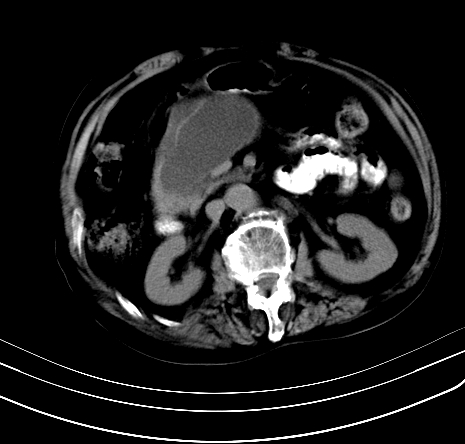

上腹部疼痛不适,行ct检查

胰腺明显肿大,密度减低,考虑慢性胰腺炎,假性囊肿形成不除外。

胰腺明显肿大,考虑慢性胰腺炎假性囊肿形成,不除外胰腺癌可能。

胰腺较明显扩大,胰周有渗出;肾周筋膜有增厚渗出,以左肾为著。应考虑急性胰腺炎。

慢性胰腺炎,假囊肿形成,脂肪肝。